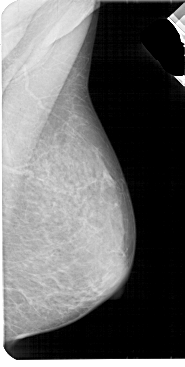

A_1947_1.LEFT_MLO

LEFT_MLO LINES 5491 PIXELS_PER_LINE 2761 BITS_PER_PIXEL 12 RESOLUTION 43.5 OVERLAY